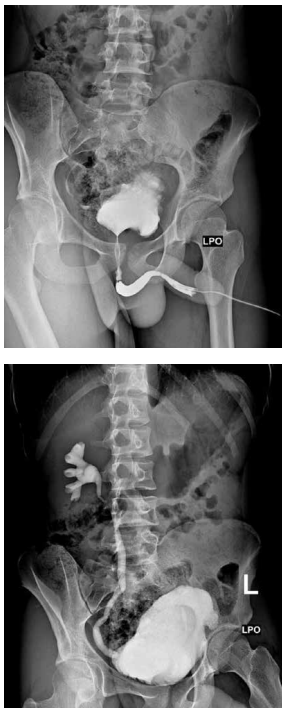

Criança de 8 anos, sexo masculino, vem apresentando história de infecção do trato urinário de repetição com relato de internação há 2 meses por febre

alta e dor lombar. Foi encaminhada ao setor de

radiologia pediátrica para investigação.

Após a análise do exame, pode-se afirmar que: